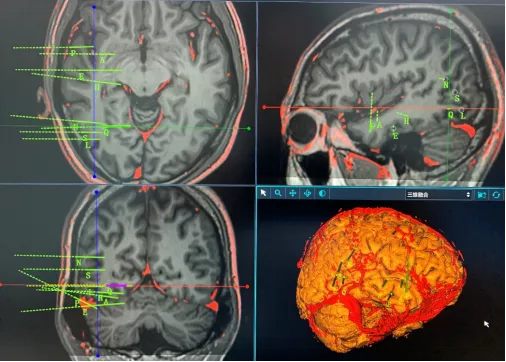

立体定向脑电图技术(stereo-electroencephalography, SEEG)是一种微创的癫痫定位评估方法。该技术最早由法国学者Bancaud和Talairach提出,通过立体定向方式植入脑深部电极,记录癫痫异常放电的起源与传播路径,从时间与空间两个维度进行评估,从而实现对癫痫病灶的精准定位。

通过术后对大脑三维立体网络的定位分析,对于病灶明确、局限的患者,可仅对癫痫灶进行毁损或切除,尽可能保留周围正常的脑组织结构,实现微创治疗。此外,对于位于功能区的癫痫灶,可通过颅内电极电刺激进一步验证手术方案,避免损伤重要神经功能,显著降低手术风险。

术前规划:多模态影像融合,重建大脑三维解剖结构